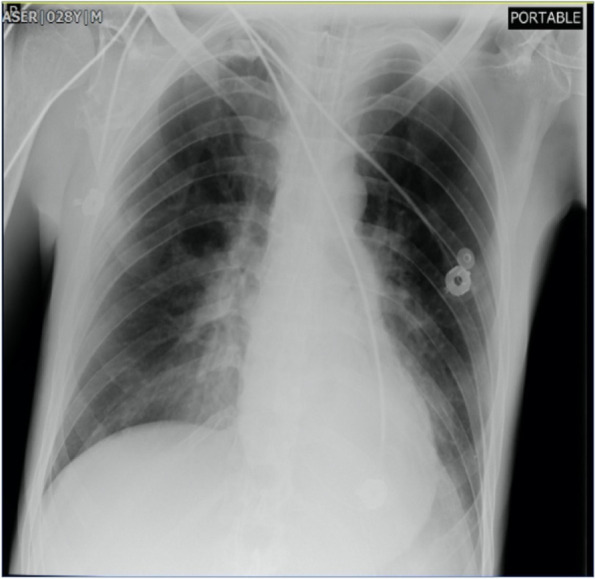

He was intubated and femoral catheterization was performed. Three vials of bicarbonate were intravenously administered. He underwent hemodialysis for eight hours but remained unresponsive. Serum/urine ketone and blood sugar were later returned to be positive and 411 mg/dL, respectively, indicating the possible presence of DKA. After initiation of insulin infusion, serum bicarbonate level started to rise. During admission, he had developed brain edema (Fig. 1). However, after appropriate treatment for DKA, the patient regained consciousness and was extubated. Since there were consolidations in his chest X-ray and lung computed tomography scan (Figs. 2 and 3), antibiotics and sepsis workup were ordered. He was initially treated by meropenem and vancomycin (for aspiration pneumonia); however, after consulting with the attending infectious disease specialist, he was started on levofloxacin. He was also receiving intravenous potassium, pantoprazole, heparin with prophylactic dose, and nebulized N-acetyl cysteine. Due to melena, endo-colonoscopy was performed but was reported to be normal. The other complication our patient experienced was deep venous thrombosis at the site of femoral catheter which mandated anticoagulation therapy with heparin drip. Diabetic ketoacidosis re-occurred twice more during the hospitalization. With the legitimate dose of methadone prescribed by psychiatrics, DKA completely resolved, and he was discharged home completely symptom-free after four weeks. Serial venous blood gas analysis, blood sugar and selected lab tests of the patient during hospital admission are shown in Figs. 4 and 5 and Table 2.

Fig. 1.

Brain computed tomography scan of the patient